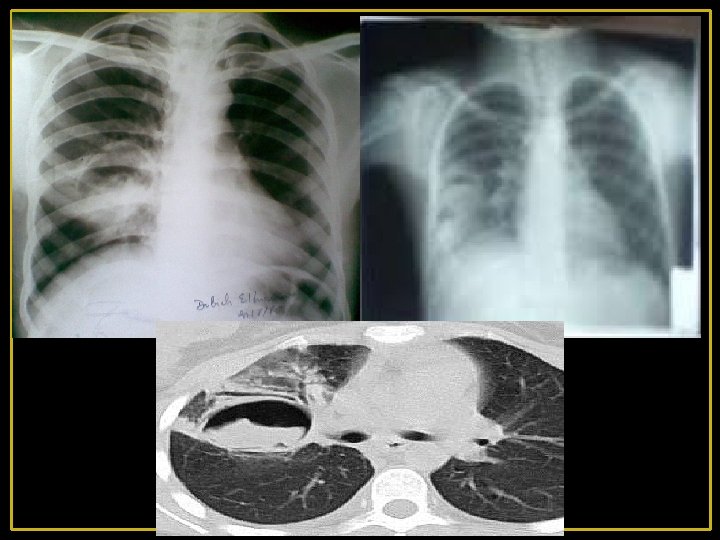

Abcès pulmonaire - Cavité (unique ou multiple) remplie de pus, secondaire à une nécrose du parenchyme pulmonaire - Se développe généralement au sein d'un foyer pneumonique - La fréquence de la cavitation dépend de la nature du germe (++ staphylocoque, les germes aérobies à Gram négatif et les germes anaérobies - Paroi : limite interne irrégulière La TDM permet de différencier un abcès pulmonaire d'un empyème : À la différence de l‘abcès, l’empyème, est ovale à paroi fine et régulière, se raccordant à la paroi à angle obtus et comprime le parenchyme voisin